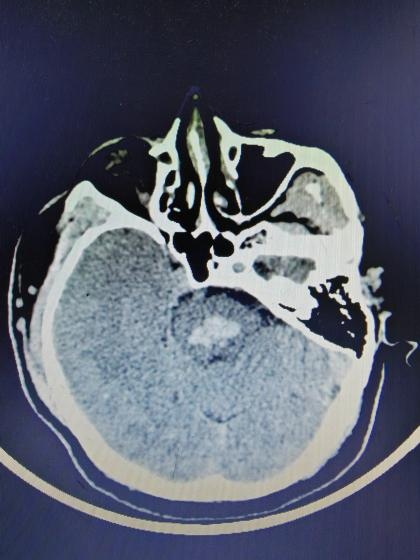

急诊CT显示:脑干(桥脑)出血,量约5ml。这是一种极其凶险的卒中类型,脑干作为生命中枢,掌管着呼吸、心跳和意识,一旦受损,后果不堪设想。入院后,小余意识障碍逐渐加重,不得不进行气管插管、呼吸机辅助通气。经过精心治疗后,小余意识逐渐恢复,并已成功脱机,肢体功能缓慢好转。

急诊CT显示:

脑干(脑桥)出血

出血量达5ml